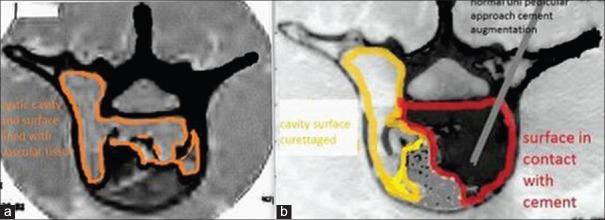

Aneurysmal bone cyst (ABC) is a vascular tumor of the spine. Management of spinal ABC still remains controversial because of its location, vascular nature and incidence of recurrence. In this manuscript, we hereby describe two cases of ABC spine treated by curettage, vertebral cement augmentation for control of bleeding and internal stabilization with two years followup. To the best of our knowledge, this is the first case report in the literature describing the role of cement augmentation in spinal ABC in controlling vascular bleeding in curettage of ABC of spine. Case 1: A 22 year old male patient presented with chronic back pain. On radiological investigation, there were multiple, osteolytic septite lesions at L3 vertebral body without neural compression or instability. Percutaneous transpedicular biopsy of L3 from involved pedicle was done. This was followed by cement augmentation through the uninvolved pedicle. Next, transpedicular complete curettage was done through involved pedicle. Case 2: A 15-year-old female presented with nonradiating back pain and progressive myelopathy. On radiological investigation, there was an osteolytic lesion at D9. At surgery, decompression, pedicle screw-rod fixation and posterolateral fusion from D7 to D11 was done. At D9 level, through normal pedicle cement augmentation was added to provide anterior column support and to control the expected bleeding following curettage. Transpedicular complete curettage was done through the involved pedicle with controlled bleeding at the surgical field. Cement augmentation was providing controlled bleeding at surgical field during curettage, internal stabilization and control of pain. On 2 years followup, pain was relieved and there was a stable spinal segment with well filled cement without any sign of recurrence in computed tomography scan. In selected cases of spinal ABC with single vertebral, single pedicle involvement; cement augmentation of vertebra through normal pedicle has an important role in surgery aimed for curettage of vertebra.

骨动脉瘤样囊肿(ABC)是一种脊柱血管性肿瘤。由于其位置、血管性质和复发率,脊柱ABC的治疗仍存在争议。在本手稿中,我们特此描述了两例经刮除术、椎体骨水泥强化以控制出血并进行内固定治疗的脊柱ABC病例,并进行了两年的随访。据我们所知,这是文献中首例描述骨水泥强化在脊柱ABC刮除术中控制血管出血作用的病例报告。病例1:一名22岁男性患者出现慢性背痛。经影像学检查,L3椎体有多个溶骨性分隔病变,无神经受压或不稳定。对L3受累椎弓根进行了经皮椎弓根穿刺活检。随后通过未受累椎弓根进行骨水泥强化。接下来,通过受累椎弓根进行经椎弓根完全刮除术。病例2:一名15岁女性出现非放射性背痛和进行性脊髓病。经影像学检查,D9有一个溶骨性病变。手术时,进行了减压、椎弓根螺钉-棒固定以及从D7到D11的后外侧融合。在D9水平,通过正常椎弓根添加骨水泥强化以提供前柱支撑并控制刮除术后预期的出血。通过受累椎弓根进行经椎弓根完全刮除术,手术野出血得到控制。骨水泥强化在刮除术、内固定和疼痛控制过程中为手术野提供了出血控制。经过两年随访,疼痛缓解,脊柱节段稳定,骨水泥填充良好,计算机断层扫描未显示任何复发迹象。在选定的单椎体、单椎弓根受累的脊柱ABC病例中,通过正常椎弓根进行椎体骨水泥强化在旨在刮除椎体的手术中具有重要作用。